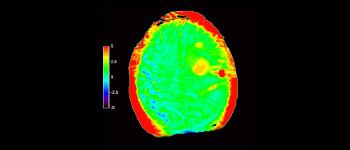

z użyciem metody 3D APT